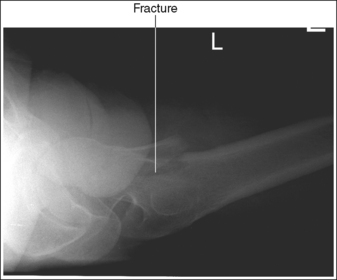

• Positioning for a fractured or dislocated proximal femur. When a patient has a dislocated or fractured proximal femur, the leg should not be internally rotated but left as is. Forced internal rotation of a dislocated or fractured proximal femur may injure the blood supply and nerves that surround the injured area. Because the patient's leg is not internally rotated when a fracture is suspected, the resulting AP hip projection may demonstrate the femoral neck with some degree of foreshortening and the lesser trochanter without femoral shaft superimposition (see Image 5).

IMAGE 5

IMAGE 14

• Positioning for a proximal femoral fracture or dislocation. When a patient has a dislocated hip or a suspected or known proximal femoral fracture, the leg should not be internally rotated, but left as is. Forced internal rotation of a dislocated hip or fractured proximal femur may injure the blood supply and nerves that surround the injured area. Because the patient's leg is not internally rotated in such cases, it is acceptable for the greater trochanter to be demonstrated posteriorly and the lesser trochanter to be superimposed over the femoral shaft (see Image 15).

IMAGE 15

The greater trochanter is demonstrated posteriorly, and the lesser trochanter is superimposed over the femoral shaft. The patient's affected leg was in external rotation.

Internally rotate the patient's leg until the femoral epicondyles are aligned parallel with the imaging table and the foot is angled internally 15 to 20 degrees from vertical, as shown in Figure 7-18.